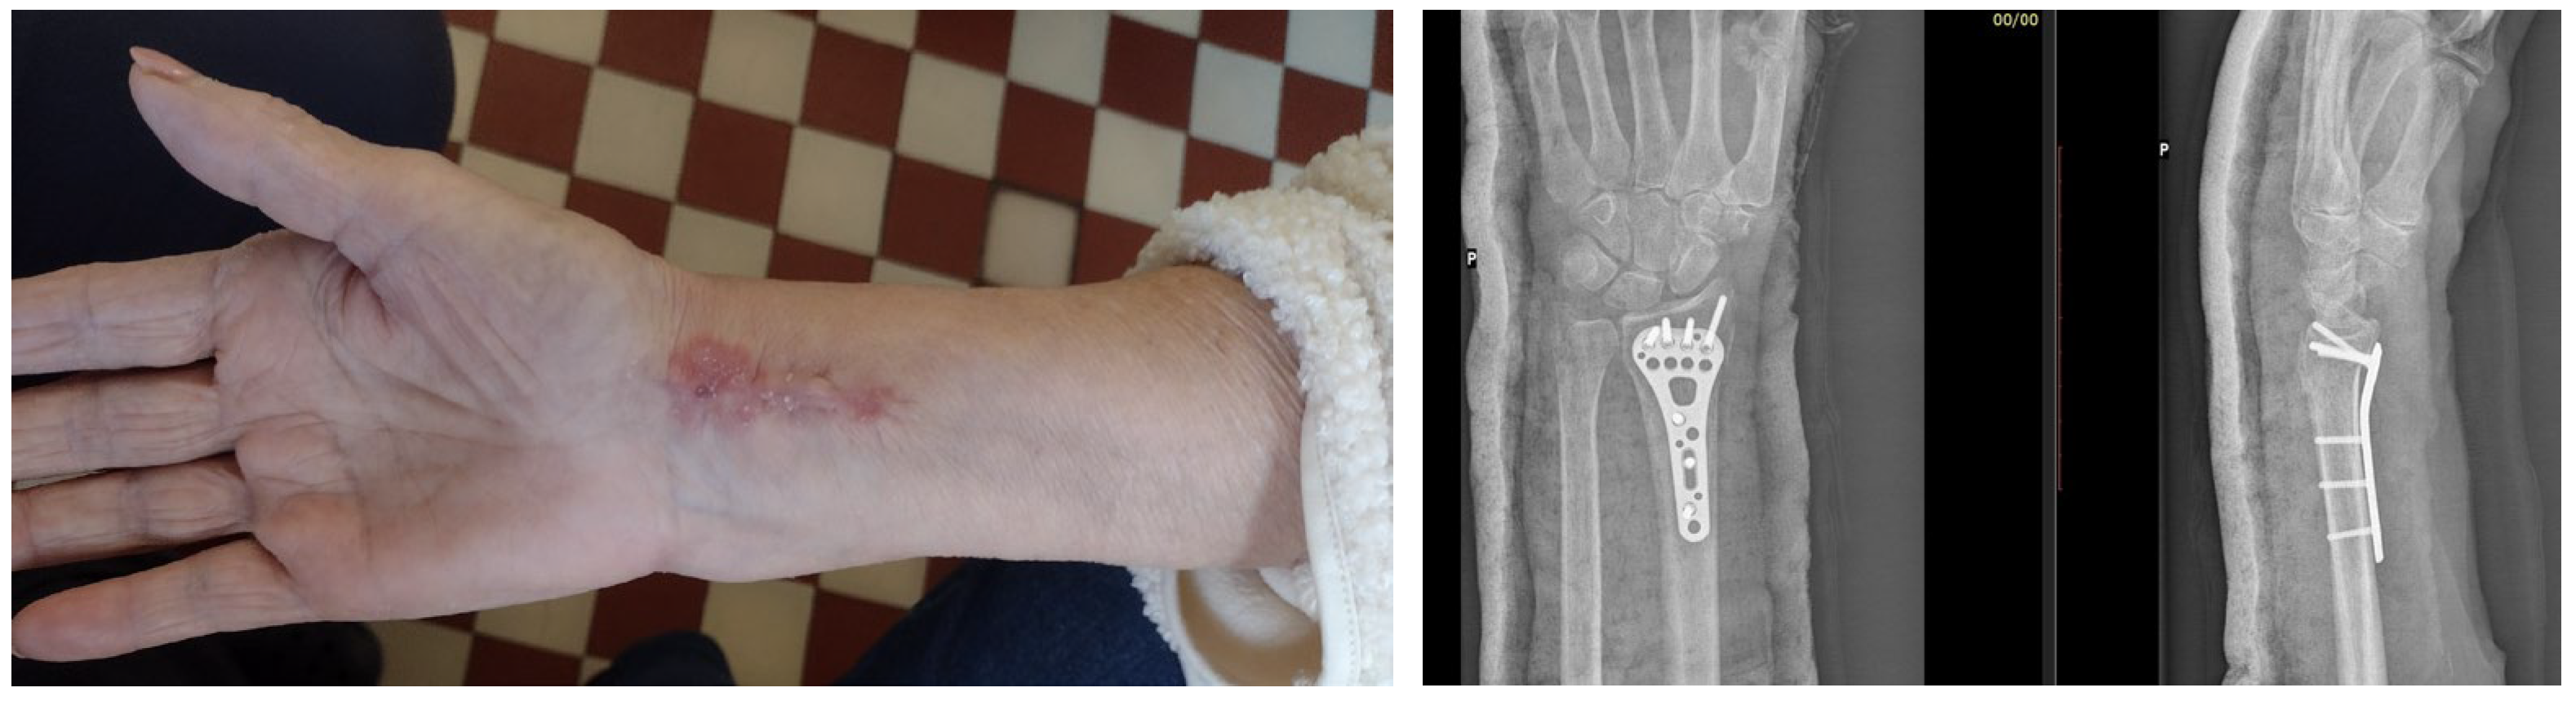

7. Macroscopic Observations of Interacted Surfaces of Removed Implants—Author Observations